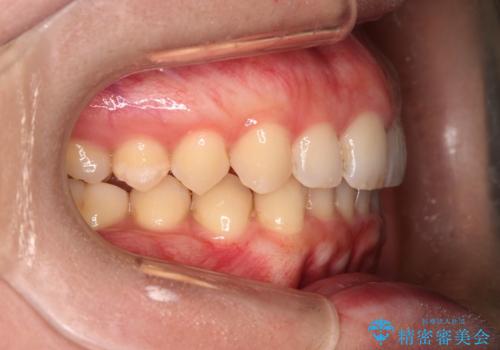

ゴム掛けを頑張っていただいたので、噛みあわせも改善され綺麗な歯並びになりました。